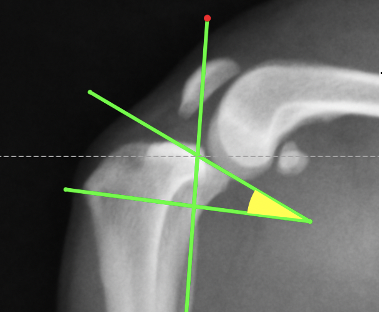

脛骨高平部角(TPA)と呼ばれる角度です。これが高いために前十字靭帯が切れやすくなります。

手術の際にはこのように様々な角度や距離を測定し、円の部分で骨切りを行います。